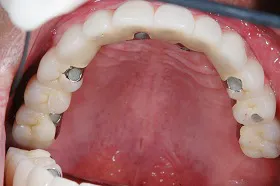

重度の歯槽膿漏のケース

■治療前

■治療後

上下に入れ歯を入れていましたが、ここ数年しっかりと噛む事がなかった患者様です。何でもおいしく食事ができるようになりたいと希望され、来院されました。

治療法としては、最小限のインプラントの本数で対応ができるように、オールオンフォーを意識した治療法で対応させて頂きました。

| 主訴 | 噛めない |

| 治療方法 | 上顎8本、下顎6本のインプラントを埋入し固定性の入れ歯で治療した |

| 治療期間 | 約1年 |

| 通院回数等 | 20回 |

| 費用 | 上顎4,130,000円 下顎3,630,000円(税込) |

| リスク・副作用 | 治療後に一時的に腫れることがある |